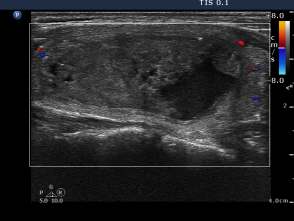

First session of sclerotherapy (second row of images):

Palpation: unchanged.

Ultrasonography remained unchanged.

We could aspirate 2 ml thick, brown cystic fluid and injected 3 mL ethanol.